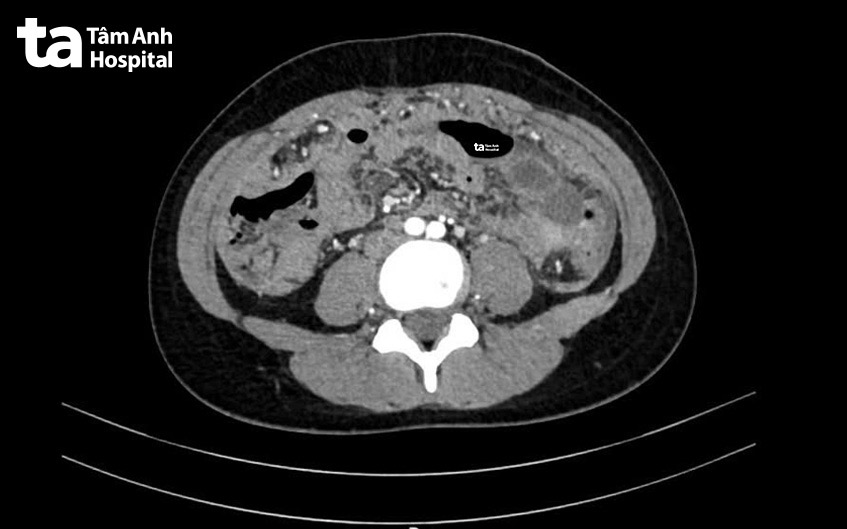

Ngày 12/9, Thạc sĩ bác sĩ chuyên khoa 1 Lưu Xuân Phát, Trung tâm Nội soi và Phẫu thuật Nội soi Tiêu hóa, Bệnh viện Đa khoa Tâm Anh TP HCM, cho biết kết quả thăm khám, siêu âm, chụp cắt lớp vi tính (CT) cho thấy bệnh nhân có tình trạng dịch trong ổ bụng.

Người bệnh được chỉ định hút dịch để làm xét nghiệm chẩn đoán. Dịch hút ra khoảng 2 lít, có màu vàng nhạt. Đây là nguyên nhân khiến người bệnh tăng cân dù có biểu hiện chán ăn, buồn nôn. Sau khi hút hết dịch, bước đầu các triệu chứng ở người bệnh thuyên giảm.